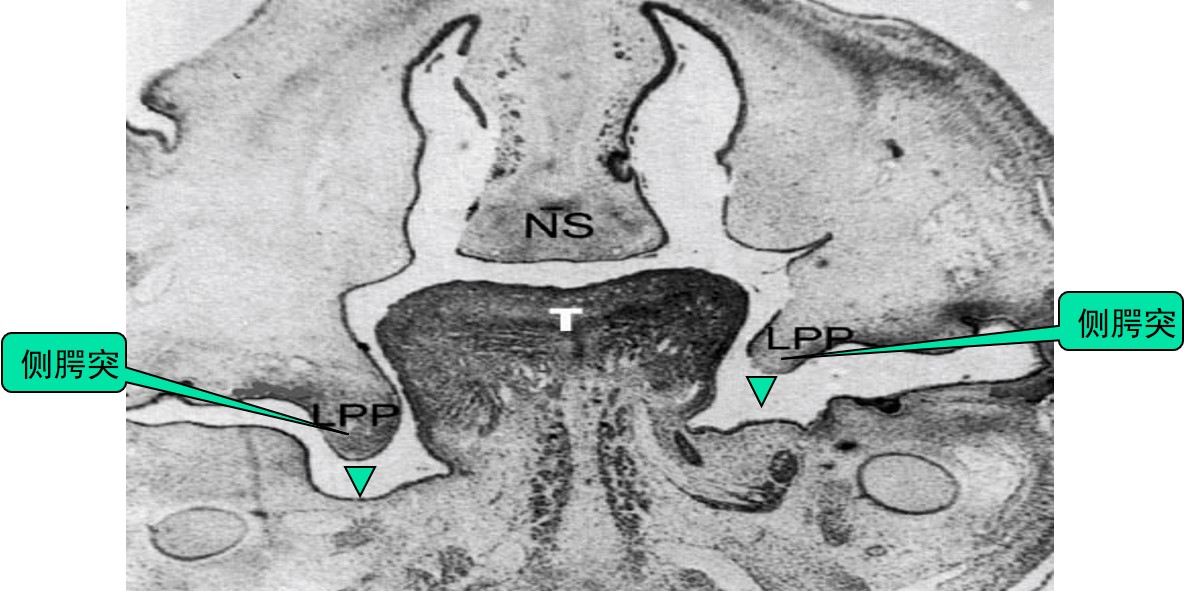

①方向:最初,侧腭突向中线方向生长,由于舌充满了口鼻腔,所以侧腭突向下或垂直方向生长,位于舌的两侧(图1.3-2),胚胎第8周,舌逐渐变扁平,位置下降,侧腭突向水平方向转动并向中线生长(图1.3-3)。

图1.3-2 侧腭突垂直方向生长